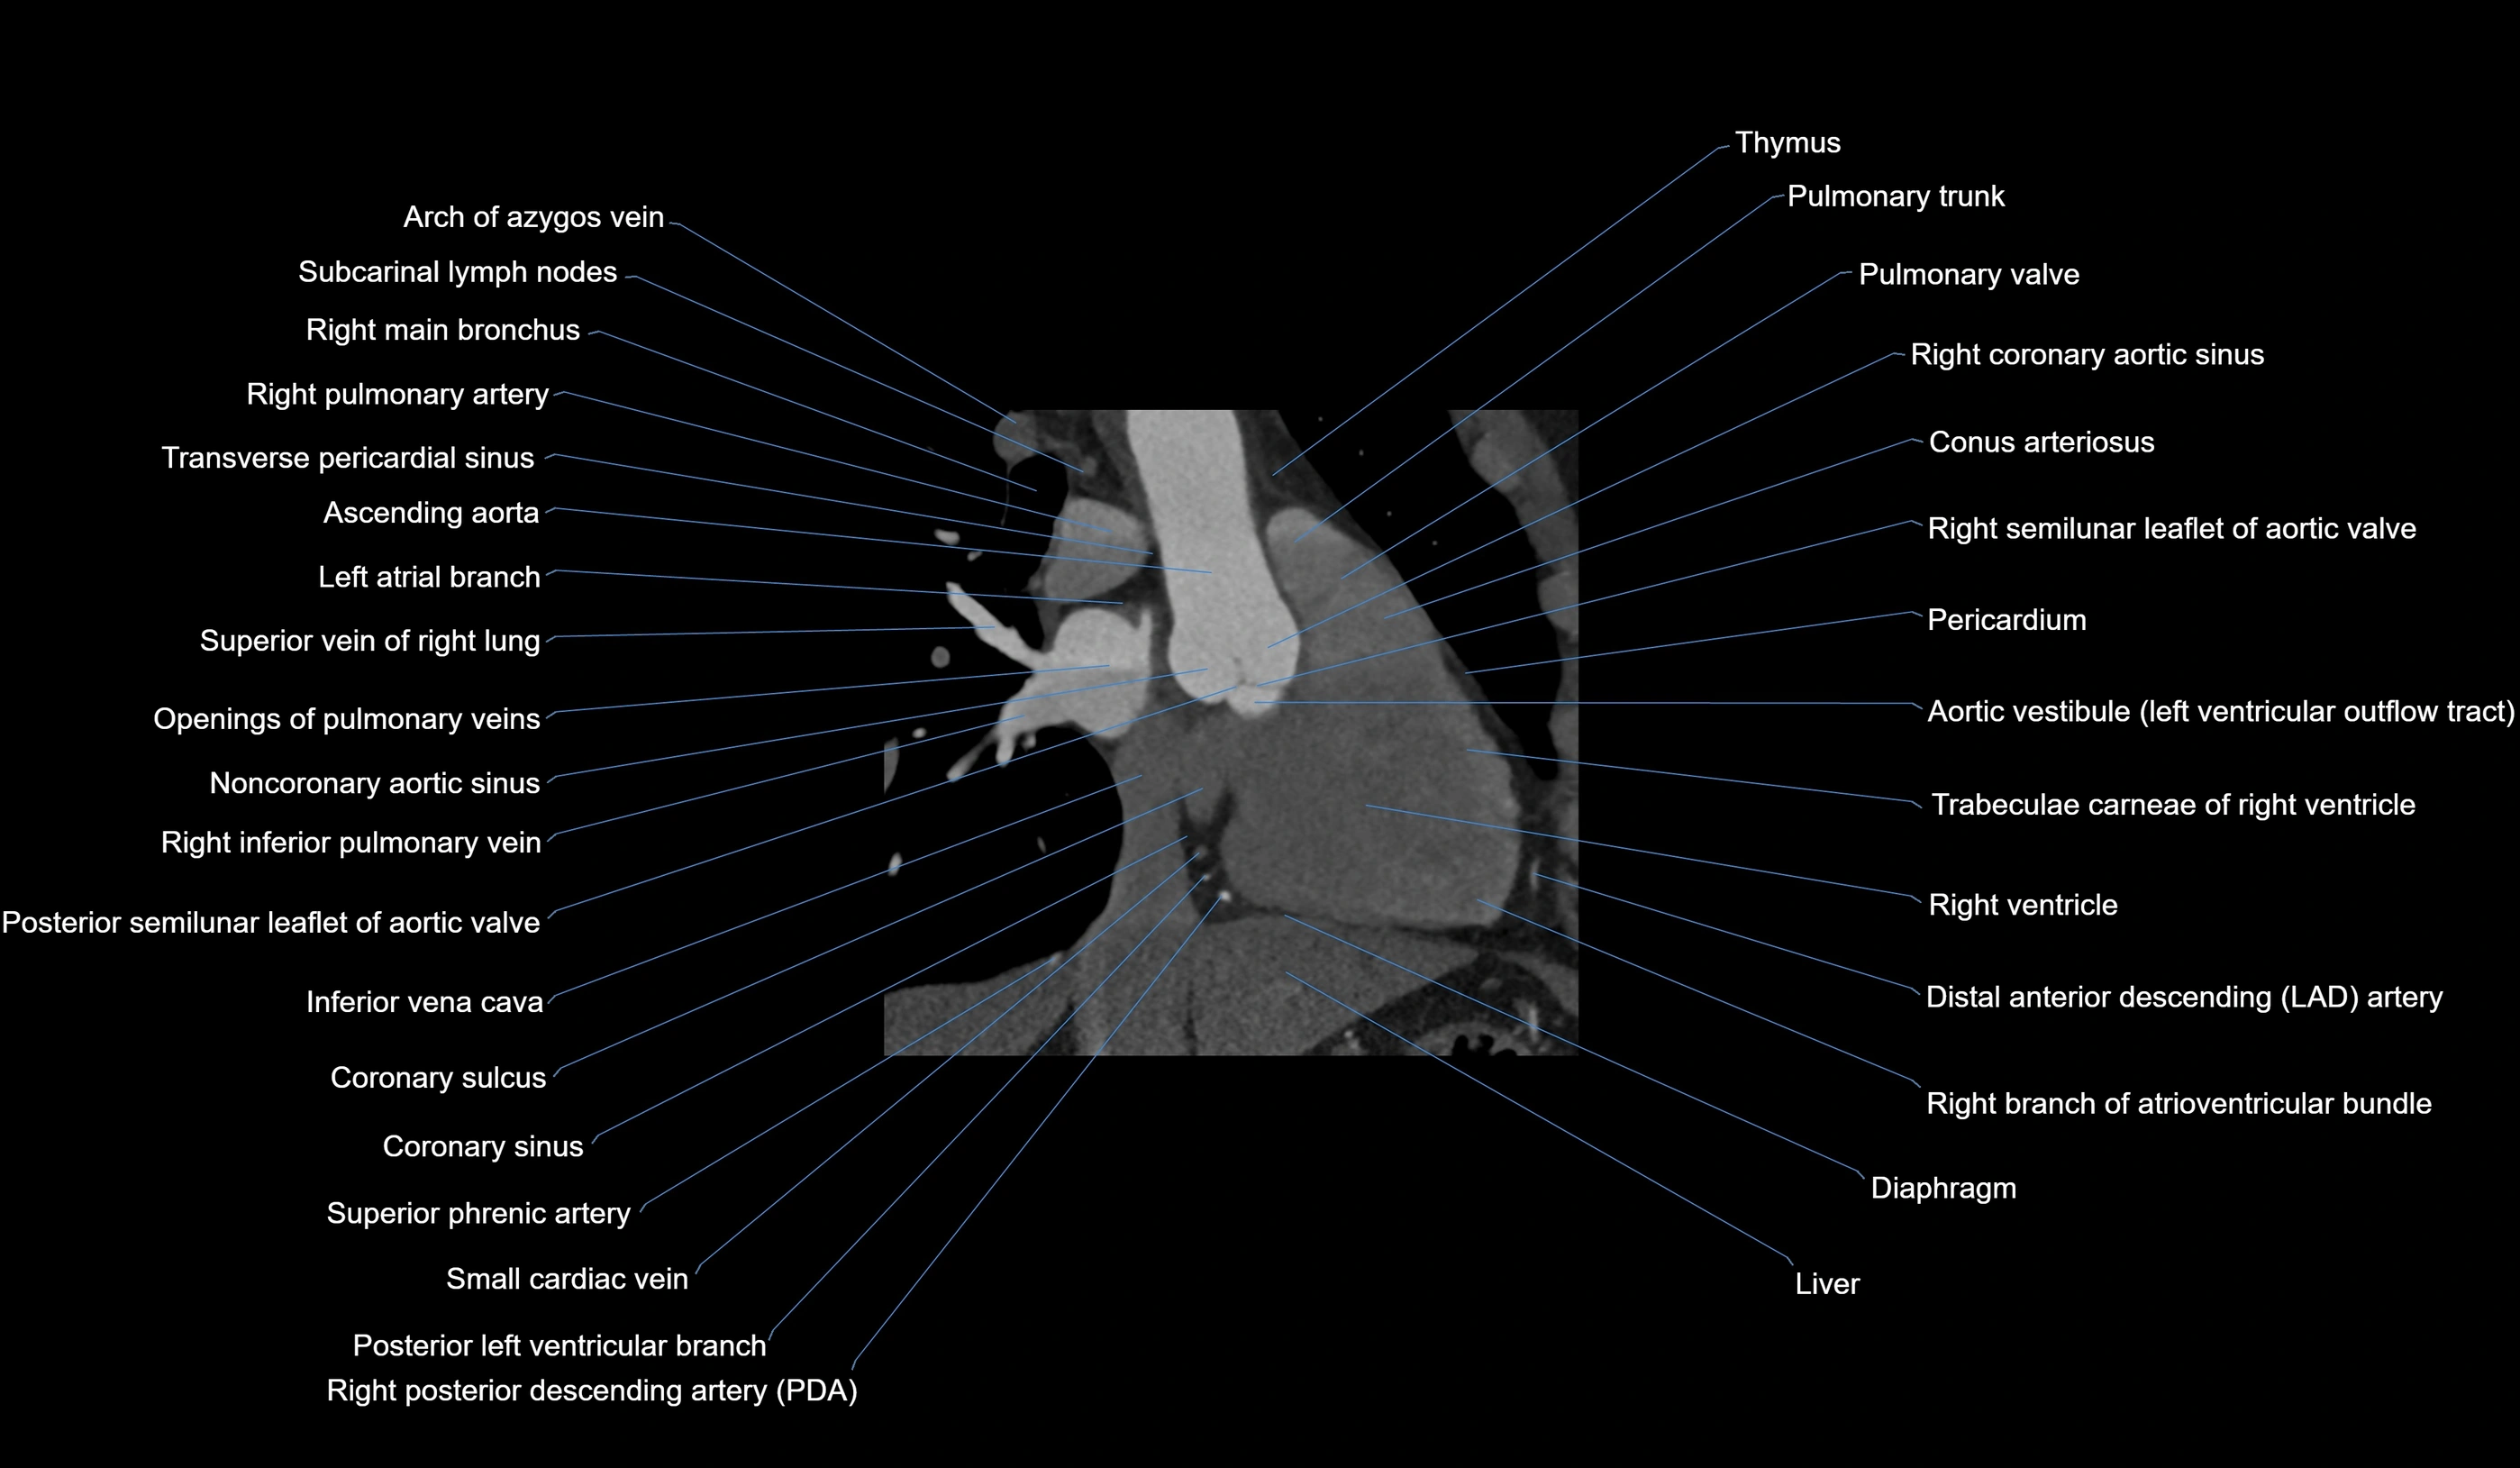

CT images